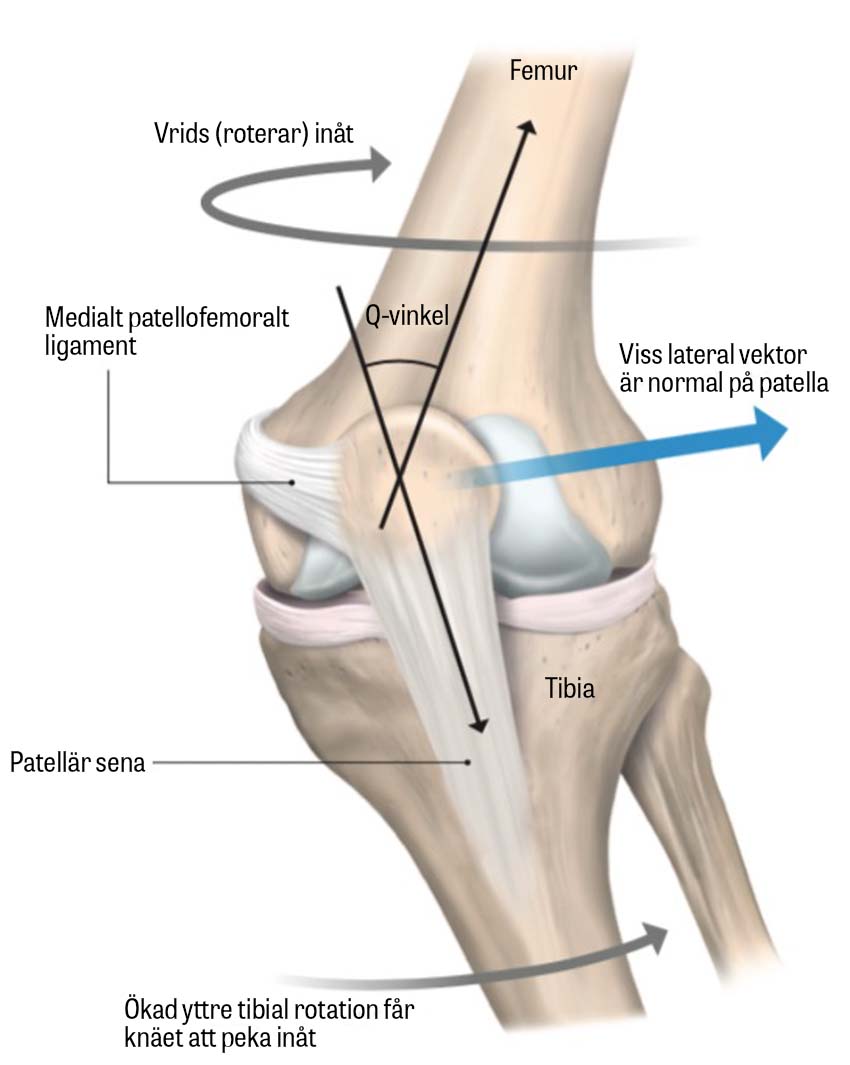

Q-vinkel. Mått på vinkeln mellan höften, patella och tuberositas tibiae, som mäter samma patoanatomi som TT–TG, men allt mer har övergetts, då det är svårt att mäta säkert och anses otillförlitligt.

Anatomisk bild över patellofemorala leden, där de viktiga strukturena relaterade till leden är illustrerade. En förstorad Q-vinkel innefattar en onormal rörelse av patella i förhållande till m quadriceps femoris och därtill en ökad risk för patellaluxationer. Mediala patellofemorala ligamentet, vars ursprung och infästning återfinns på den anteromediala delen av patella respektive den mediala femurepikondylen, fungerar som en passiv motstående kraft mot lateral försjuktning av patella.

Illustration:

Pontus Andersson